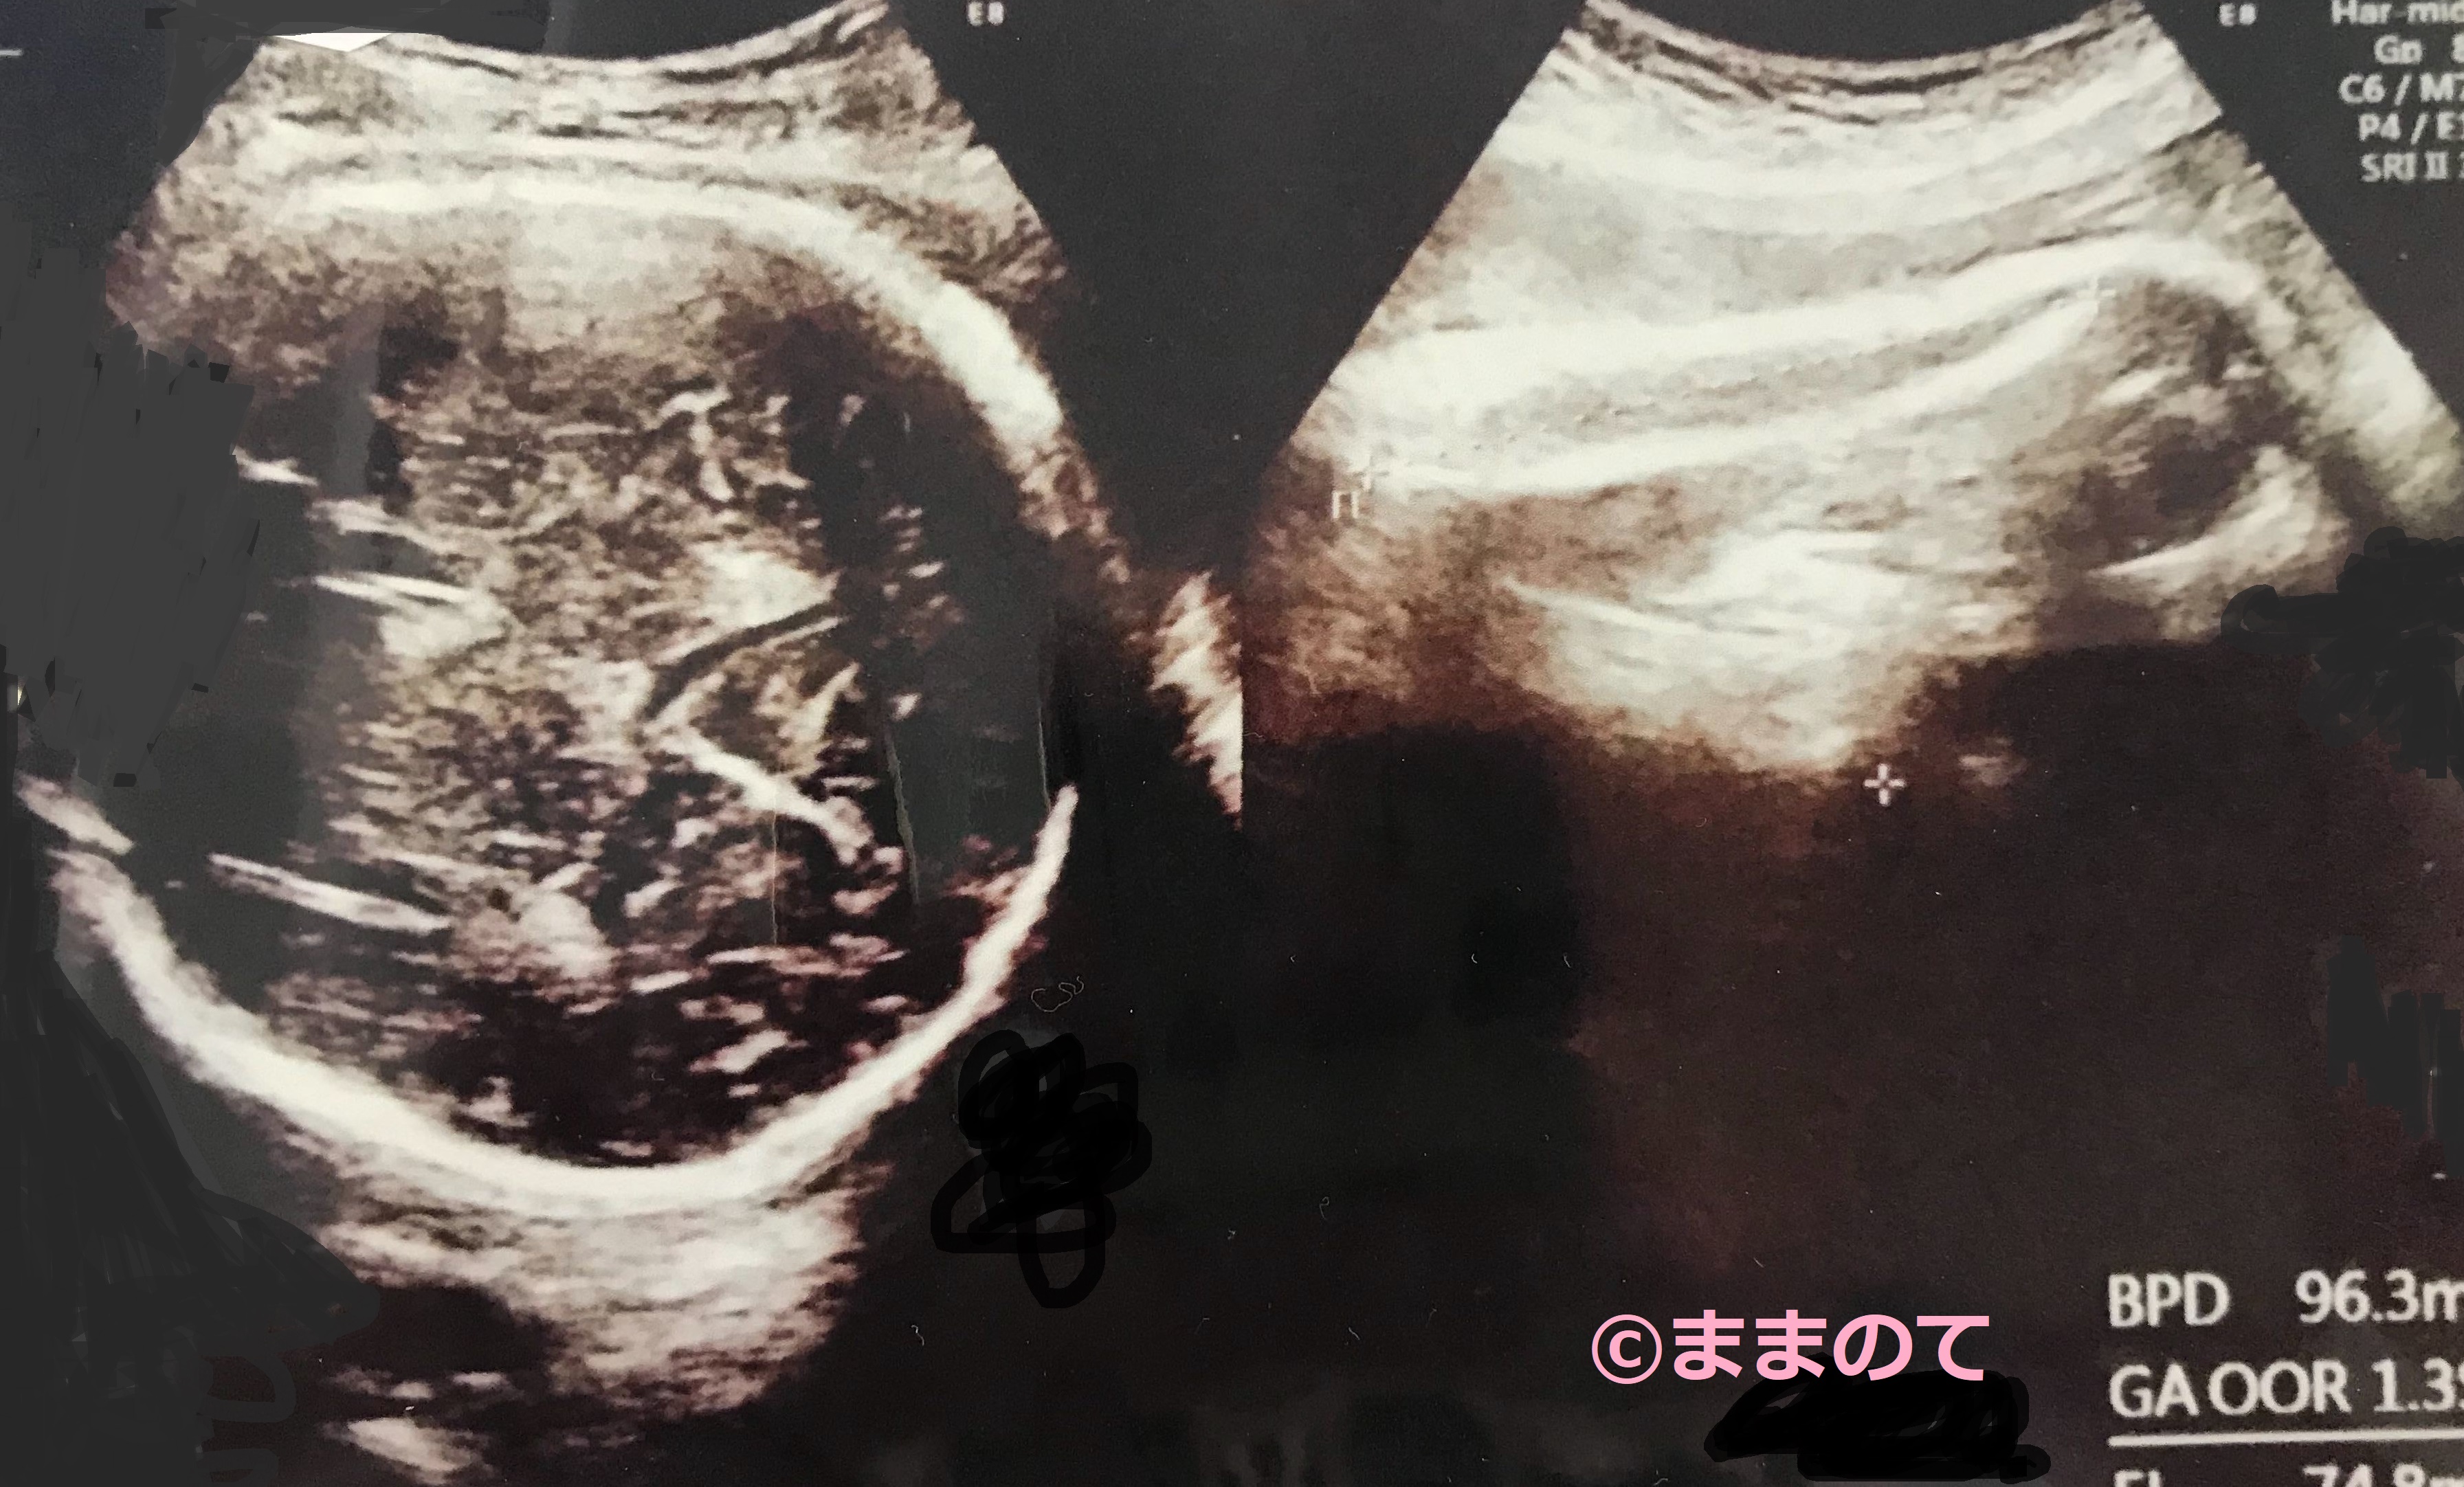

妊娠39週の赤ちゃんのエコー画像

この時期の赤ちゃんは骨盤の中におりてきています。エコー写真には身体の一部しか写りませんが、条件が合えば鼻筋や唇の形が見られます。小さな豆粒のようだった赤ちゃんが、エコー写真に写り切らないほどの大きさに成長を遂げた10ヶ月。もうすぐ会えるのが楽しみですね。